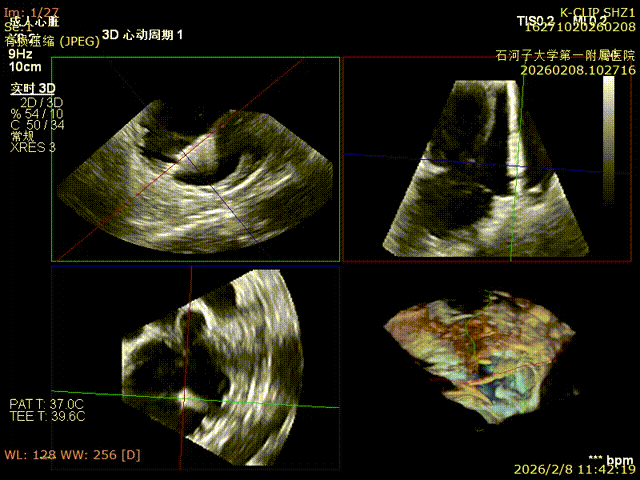

The second device is three-dimensionally aligned to the anteroposterior commissure

Second device: adjust trajectory and anchor

The second device is positioned against the annulus

Close the clamp for the second device